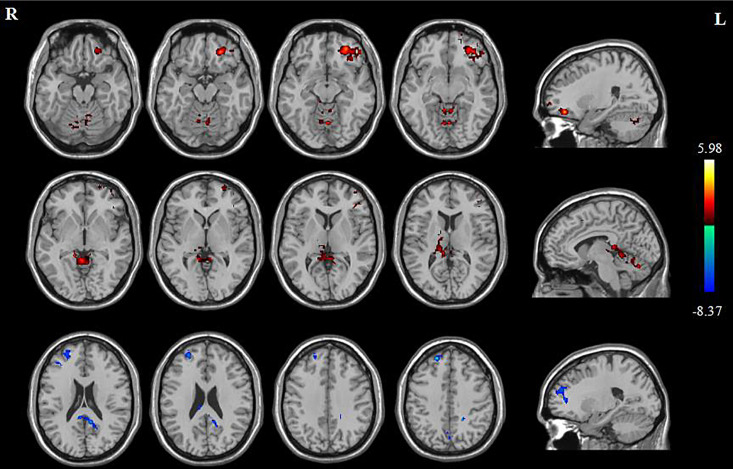

Methods: Twenty-two mild cognitive impairment participants who were randomly assigned to the real and the sham groups received 10 sessions and sham-controlled 10 Hz rTMS over the DLPFC. All patients underwent cognitive assessments and diffusion tensor imaging scans before and after the intervention. Brain regions that showed significant differences in fractional anisotropy (FA) values were selected as the regions of interest to calculate the correlation with cognitive scores.

Results: In the real group, FA values in the left middle frontal gyrus and bilateral parahippocampal gyrus increased and in the right superior frontal gyrus decreased. No significant FA change was detected in the sham group. Furthermore, the FA value of the left middle frontal gyrus was positively correlated with Boston Naming Test (BNT) scores. The change of FA value in the right superior frontal gyrus was positively correlated with the change in the Trail Making Test (TMT-B) score.

Conclusions: This study provides new evidence for rTMS to regulate the abnormal WM microstructure in some special regions and causally ameliorate cognitive performance in MCI, which may be the underlying neural mechanism of intervention.